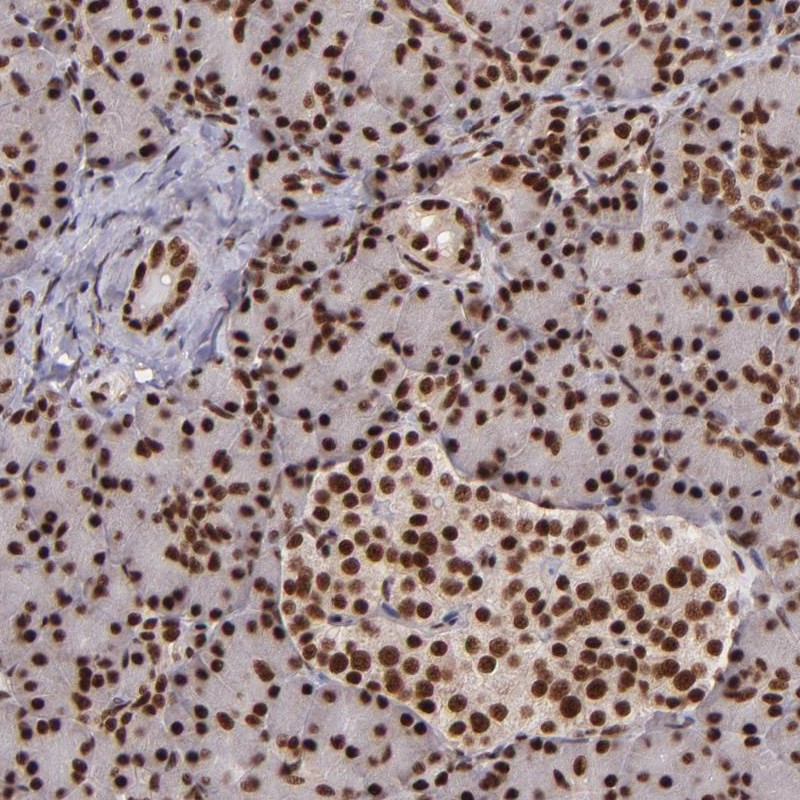

Immunohistochemical staining of human pancreas shows strong nuclear positivity in exocrine glandular cells and islet cells.